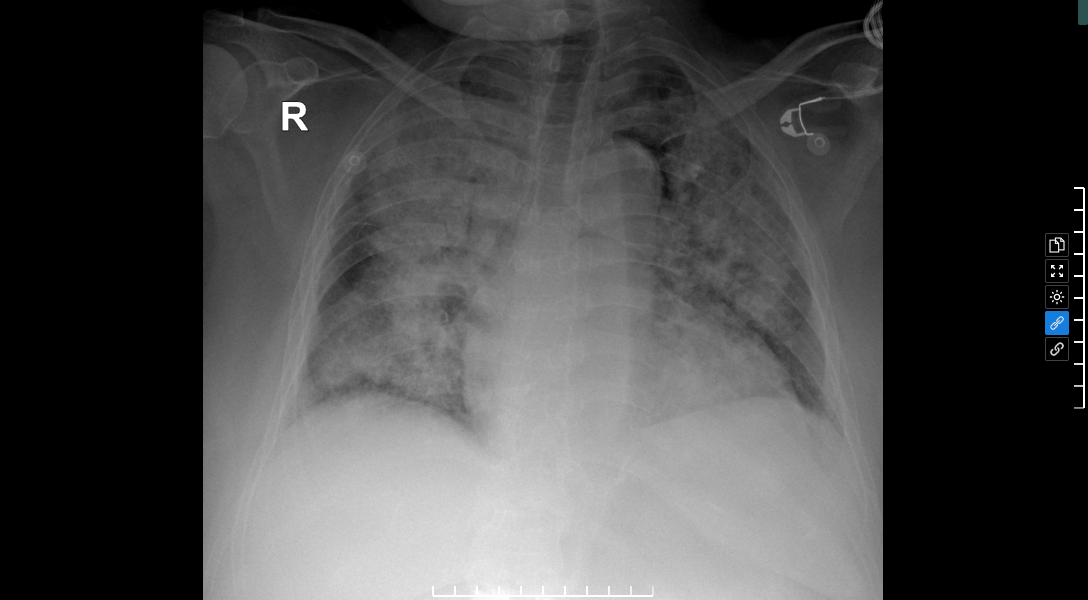

One day before hospital admission, Ms. Cham experienced fever, chills, severe coughing with thick phlegm, intense chest pain, and altered consciousness. Upon arrival at Tam Anh General Hospital Hanoi, her SpO₂ level was around 80% (healthy individuals typically have over 95%), indicating acute severe respiratory failure. Widespread consolidation interspersed with ground-glass opacities appeared in both lungs. This impaired gas exchange, reducing oxygen supply to the brain and causing the patient to lose consciousness. Doctors diagnosed pneumonia, with tests positive for the bacterium *Streptococcus pneumoniae*. A high lactate level of 6.58 confirmed septic shock, causing her blood pressure to drop significantly to 78/45 mmHg.

X-ray image shows dense lesions in both lungs. *Photo: Tam Anh General Hospital*